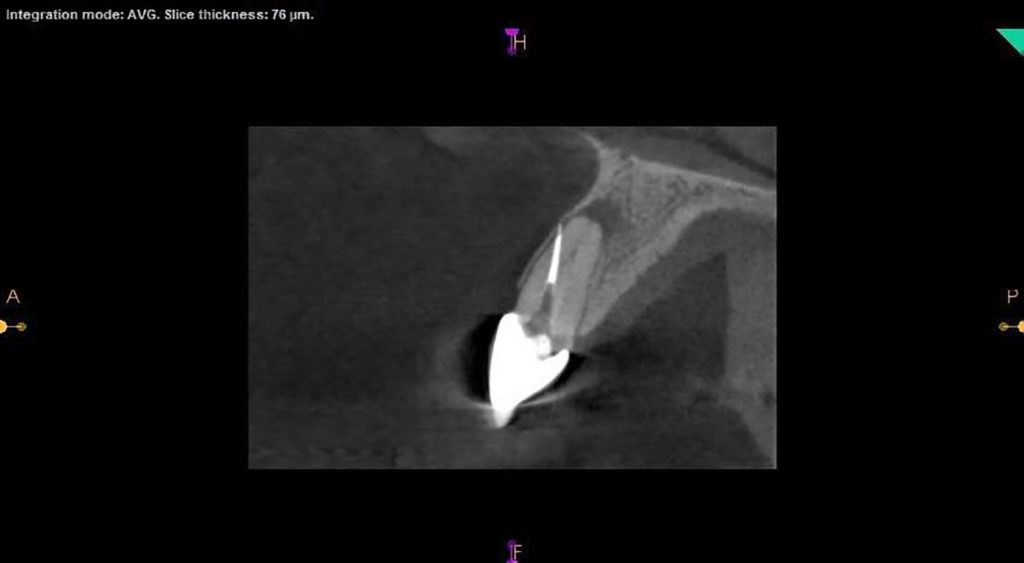

Fun retreatment. Patient had RCT on 9, which was retreated by another endodontist 5 years ago. Patient developed pain and swelling in the area. CBCT revealed a transported canal with a perforation. I was able to locate the canal and hopefully save the tooth!